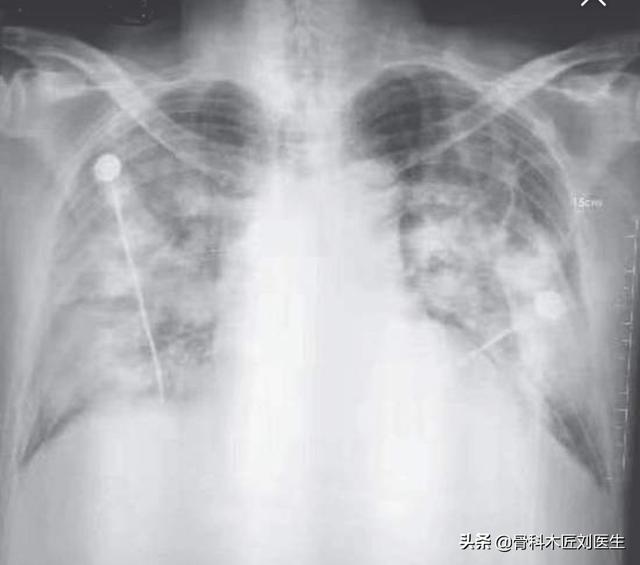

胸部レントゲン写真や肺のCT画像では、肺の外側の帯状に認められる斑状の影や、重症例では肺の固い影が認められることがある。

2.肺炎の画像的特徴を有する:肺に炎症性変化があることを意味し、肺の外側の帯状に明らかな複数の小さな斑状影や間質性変化、さらには両肺に複数の地中影や浸潤影などの変化を示します。ウイルスが肺に侵入した後、肺にうっ血や水腫が生じ、X線やCTで高密度の影が観察されるからです。

②胸部CTを撮影すると、初期には多発性の斑状陰影や間質性変化を示唆することがあり、肺外帯に明らかで、その後の検討で両肺に多発性の地中影や浸潤影が生じ、重症例では固形肺病変が出現する。

②.肺炎の画像的特徴が胸部に認められる。

初期には複数の小さな斑状影と間質性変化を呈し、両肺に多発する地硝子影や浸潤影へと進行し、重症例では肺に固形変化が生じ、一般に「白い肺」と呼ばれる状態になることもある。